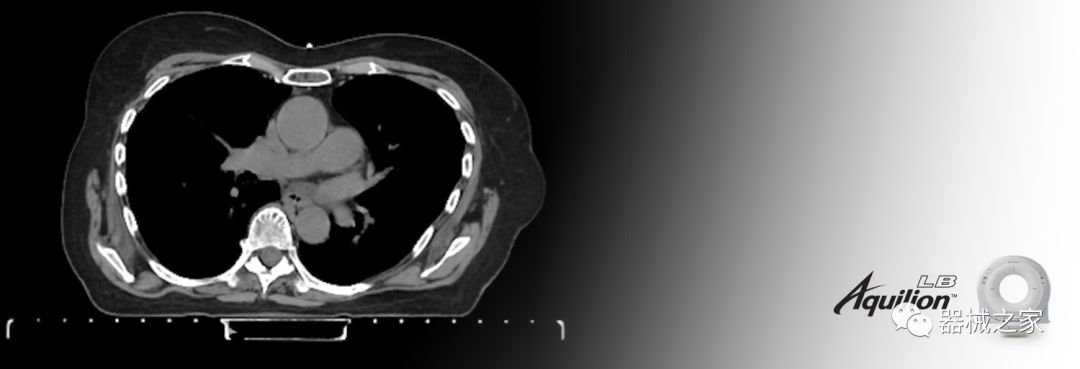

在以患者為中心的放射腫瘤學(xué)領(lǐng)域,計算機斷層掃描(CT)的可訪(fǎng)問(wèn)性,可重復性和靈活性至關(guān)重要。為了建立這些價(jià)值,佳能醫療系統美國公司現在正在擴大其放射腫瘤學(xué)CT模擬產(chǎn)品,包括Aquilion Prime SP和Aquilion Lightning 80高級CT系統。除了Aquilion LB之外,Aquilion Prime SP和Aquilion Lightning 80現在還包括放射治療(RT)選項,可為腫瘤學(xué)規劃提供高質(zhì)量的CT成像和精密工具。

Aquilion LB專(zhuān)為滿(mǎn)足腫瘤學(xué)挑戰而設計,同時(shí)優(yōu)先考慮患者護理。Aquilion LB的內徑為90 cm,能夠幫助復雜的患者設置并提高患者的舒適度。CT模擬定位可以輕松鏡像放射治療定位,更加自信。該系統采用0.5 mm x 16排(32層)PUREViSION探測器技術(shù),70 cm視野,AIDR 3D和SEMAR技術(shù)。